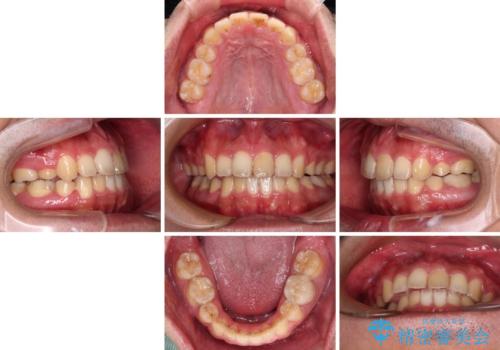

後戻りでデコボコの前歯 インビザライン矯正治療

- 高校時代に行った抜歯矯正が後戻りをしたとのことで来院された患者様です。

再矯正であることから、目立ちにくい装置を希望されたため、インビザラインにて矯正治療を行うこととしました。

下顎骨が左側に変位しているため、正中が合わないことは予想できましたが、歯列が整った後も咬み合わせが安定せず、咬み合わせを落ち着かせるために1年以上の期間を要しました。

噛みにくさの改善に時間がかかってしまうことがインビザラインの欠点の1つといえます。